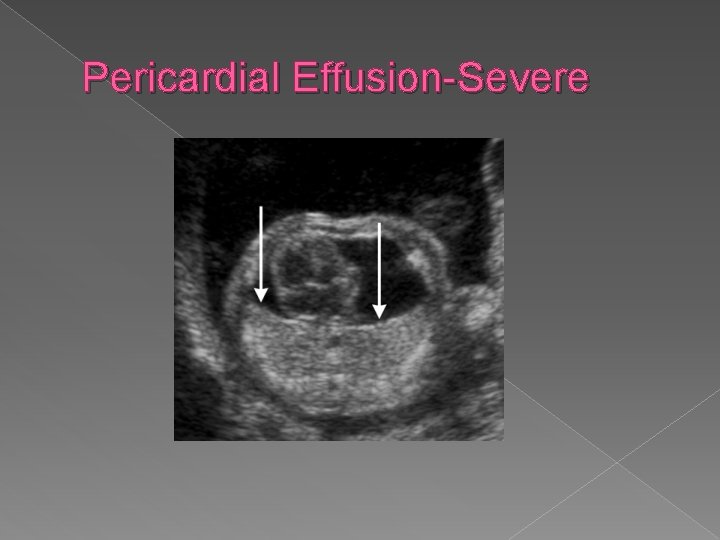

Pericardial effusion � “Fluid around the heart" is an abnormal accumulation of fluid in the pericardial cavity. Because of the limited amount of space in the pericardial cavity, fluid accumulation will lead to an increased intrapericardial pressure and this can negatively affect heart function. When there is a pericardial effusion with enough pressure to adversely affect heart function, this is called cardiac tamponade. Pericardial effusion usually results from a disturbed equilibrium between the production and re-absorption of pericardial fluid, or from a structural abnormality that allows fluid to enter the pericardial cavity.

Pericardial Effusion-Severe